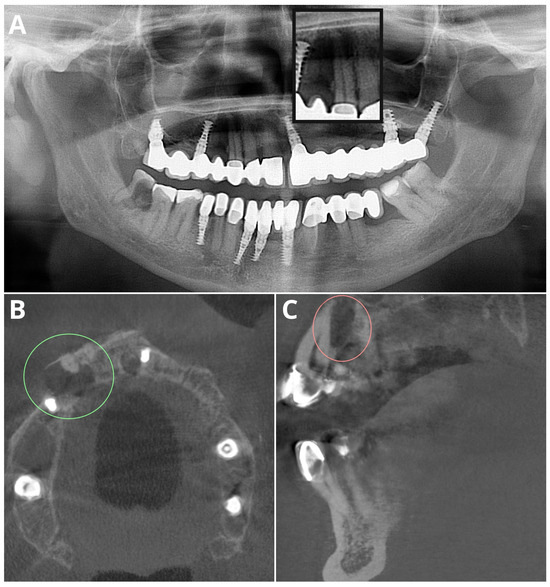

Periapical Lesions in Panoramic Radiography and CBCT Imaging—Assessment of AI’s Diagnostic Accuracy

2. Materials and Methods

2.2. Image Acquisition and Post-Processing